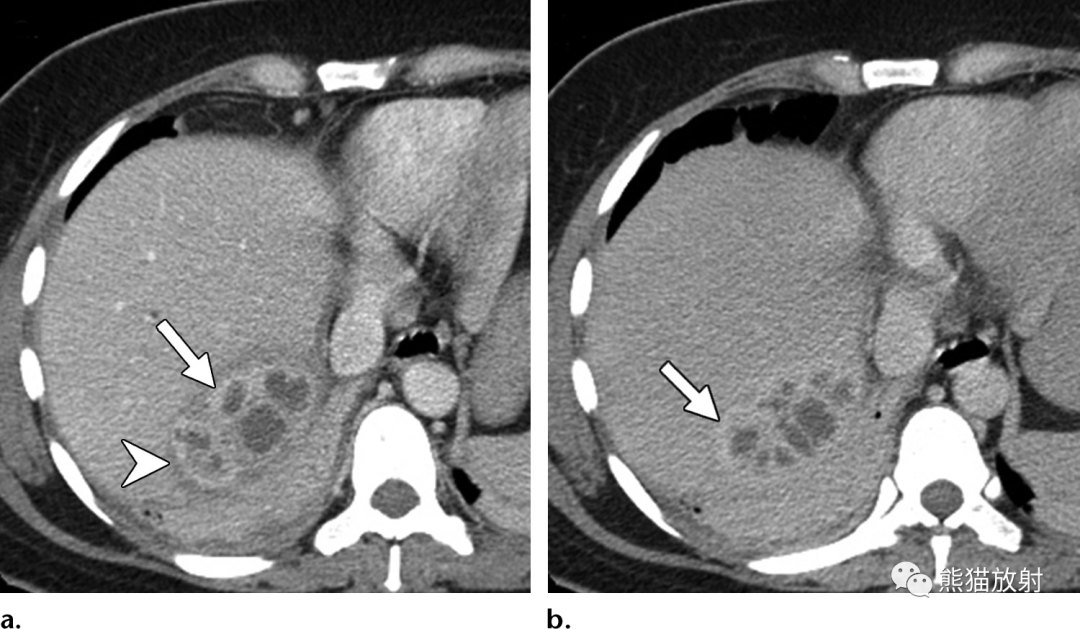

图片

69岁男性,胆总管结石患者,发热,实性机化性肝脓肿。(a) 动脉早期CT图像显示具有“靶征”表现的结节,中心早期强化,与肝实质相似,边缘密度较低。(b) 延迟期病灶中心呈等密度,外周环状强化(箭头)。由于脓液吸收而无中心液体内容物,使脓肿呈实性外观,可能难以与肝内胆管细胞癌相鉴别。